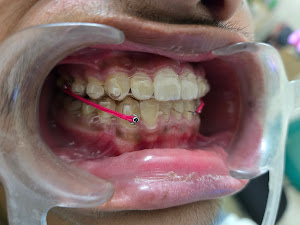

Cover photo of Horizon Dental | Invisalign Clinic | Best Dentist in Padmanabhanagar